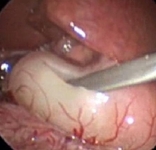

Pyloric stenosis

Laparoscopic port placement.

From the collection of Dr Jeffrey S. Upperman; used with permission